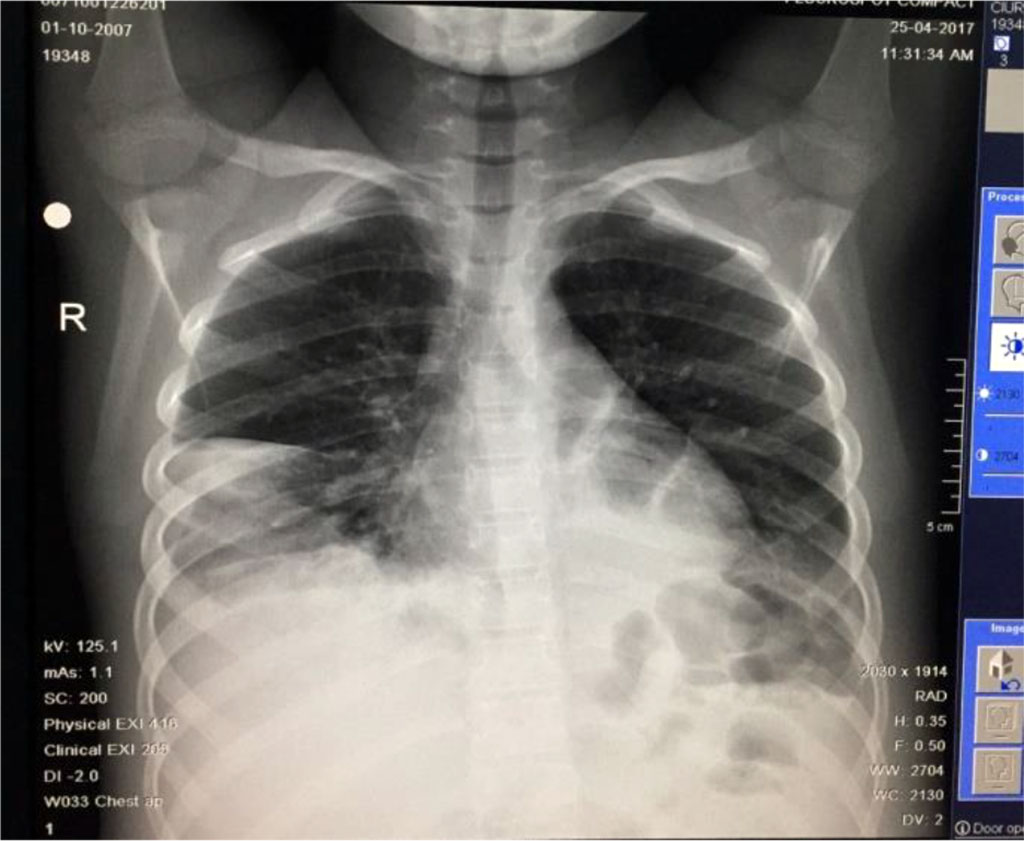

Seven days after the pleural drainage, another chest x-ray was performed. It revealed the maintaining of a non-homogeneous opacity in medium 2/3 of the right hemithorax (Fig. 8). Thus, a video-assisted thoracoscopy (VAT) pleuropulmonary decortication was done (Fig. 9). A subsequent chest x-ray revealed an ameliorated image (Fig. 10). Post-operatory evolution was slowly favorable despite the association between large spectrum antibiotic therapy and systemic antifungal therapy. The patient also needed supportive with rehydration perfusion, immunotherapy and blood transfusion for about one month.

Fig. 10. Same case as in Fig 4-9 after 1 month of treatment